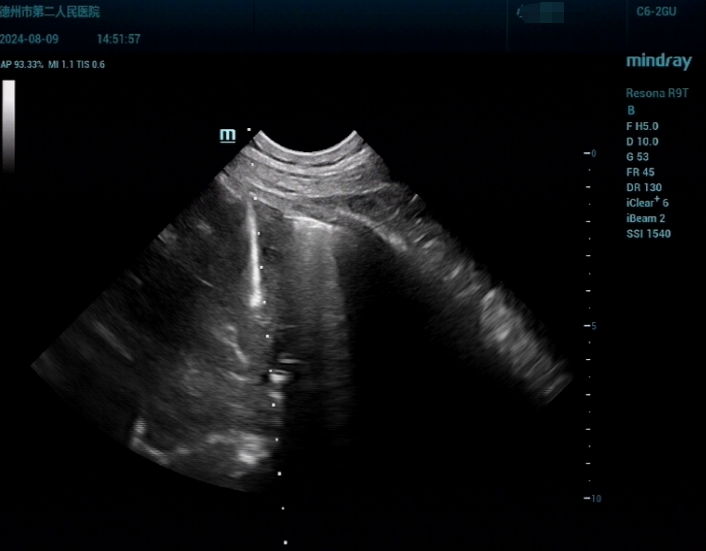

为进一步明确肿物性质,以便制定接下来的治疗方案,李阿姨在医生的建议下来到了超声医学科做检查。超声医学科副主任杨伟伟在了解了李阿姨的情况后,决定采用超声引导下纵隔穿刺活检术,获取肿物组织样本,以便明确肿物是“良”还是“恶”。

手术当天,杨伟伟带领团队在超声实时引导下,精准定位了肿物位置,同时避开了周围的血管、神经,直达病灶完成穿刺,顺利完成了标本取样。杨伟伟介绍,近年来,医院超声医学科在穿刺活检及介入治疗领域积累了丰富的临床经验。科室常年开展超声实时引导下的全身各部位肿块穿刺活检术,尤其擅长在纵隔、肺部、头颅等复杂部位实施高难度、精准化的穿刺活检技术,为各类肿瘤患者的诊断和治疗提供了精准、科学的病理学诊断依据。